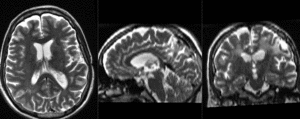

| baseline & T2 before registration (click to enlarge) | |